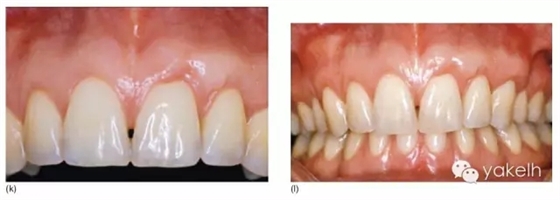

¤¤這類復雜的膜齦手術用于同時處理多個根面Ⅰ類/使Ⅱ類牙齦退縮(圖5.11a~m)。

圖5.11 (a)患者休息放松狀態(tài)下的嘴唇——上下唇不能完全閉合。(b)右上尖牙和側(cè)切牙呈Ⅰ類牙齦退縮。(c)左上頜尖牙和側(cè)切牙呈Ⅱ類牙齦退縮。(d)先用圓形眼科刀片開始做溝內(nèi)切口。(e)使用探針在袋內(nèi)垂直探查貫通隧道,越過膜齦聯(lián)合。(f)使用探針在隧道內(nèi)橫向探查貫通,保留齦乳頭尖端附著于骨面。(g)從腭部取結締組織移植物,使用絲線牽引,將厚度和大小足夠的結締組織瓣插入隧道內(nèi)。(h)通過懸吊縫合將組織瓣冠向復位,穩(wěn)定結締組織瓣。(i)術后6個月,上頜右側(cè)觀。(j)上頜左側(cè)觀,可見牙齦厚度以及色澤的協(xié)調(diào)性均得到改善。(k)術后6個月正面觀,牙敏感癥狀消失。(l)術后1年的全口影像,顯示雙側(cè)的牙齦退縮均被完全覆蓋,牙齦邊緣增厚且穩(wěn)定,與釉牙骨質(zhì)界輪廓一致,也與左側(cè)中切牙釉質(zhì)缺損輪廓一致。(m)患者嶄新的笑容,可見側(cè)切牙及尖牙的齦緣無退縮。